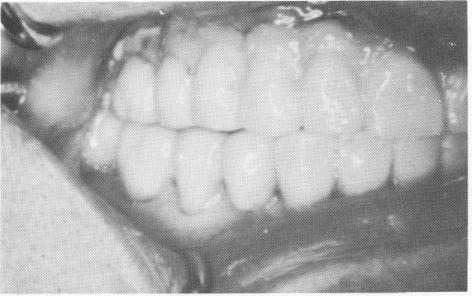

Fig. 10-263. The balanced completed prosthesis.